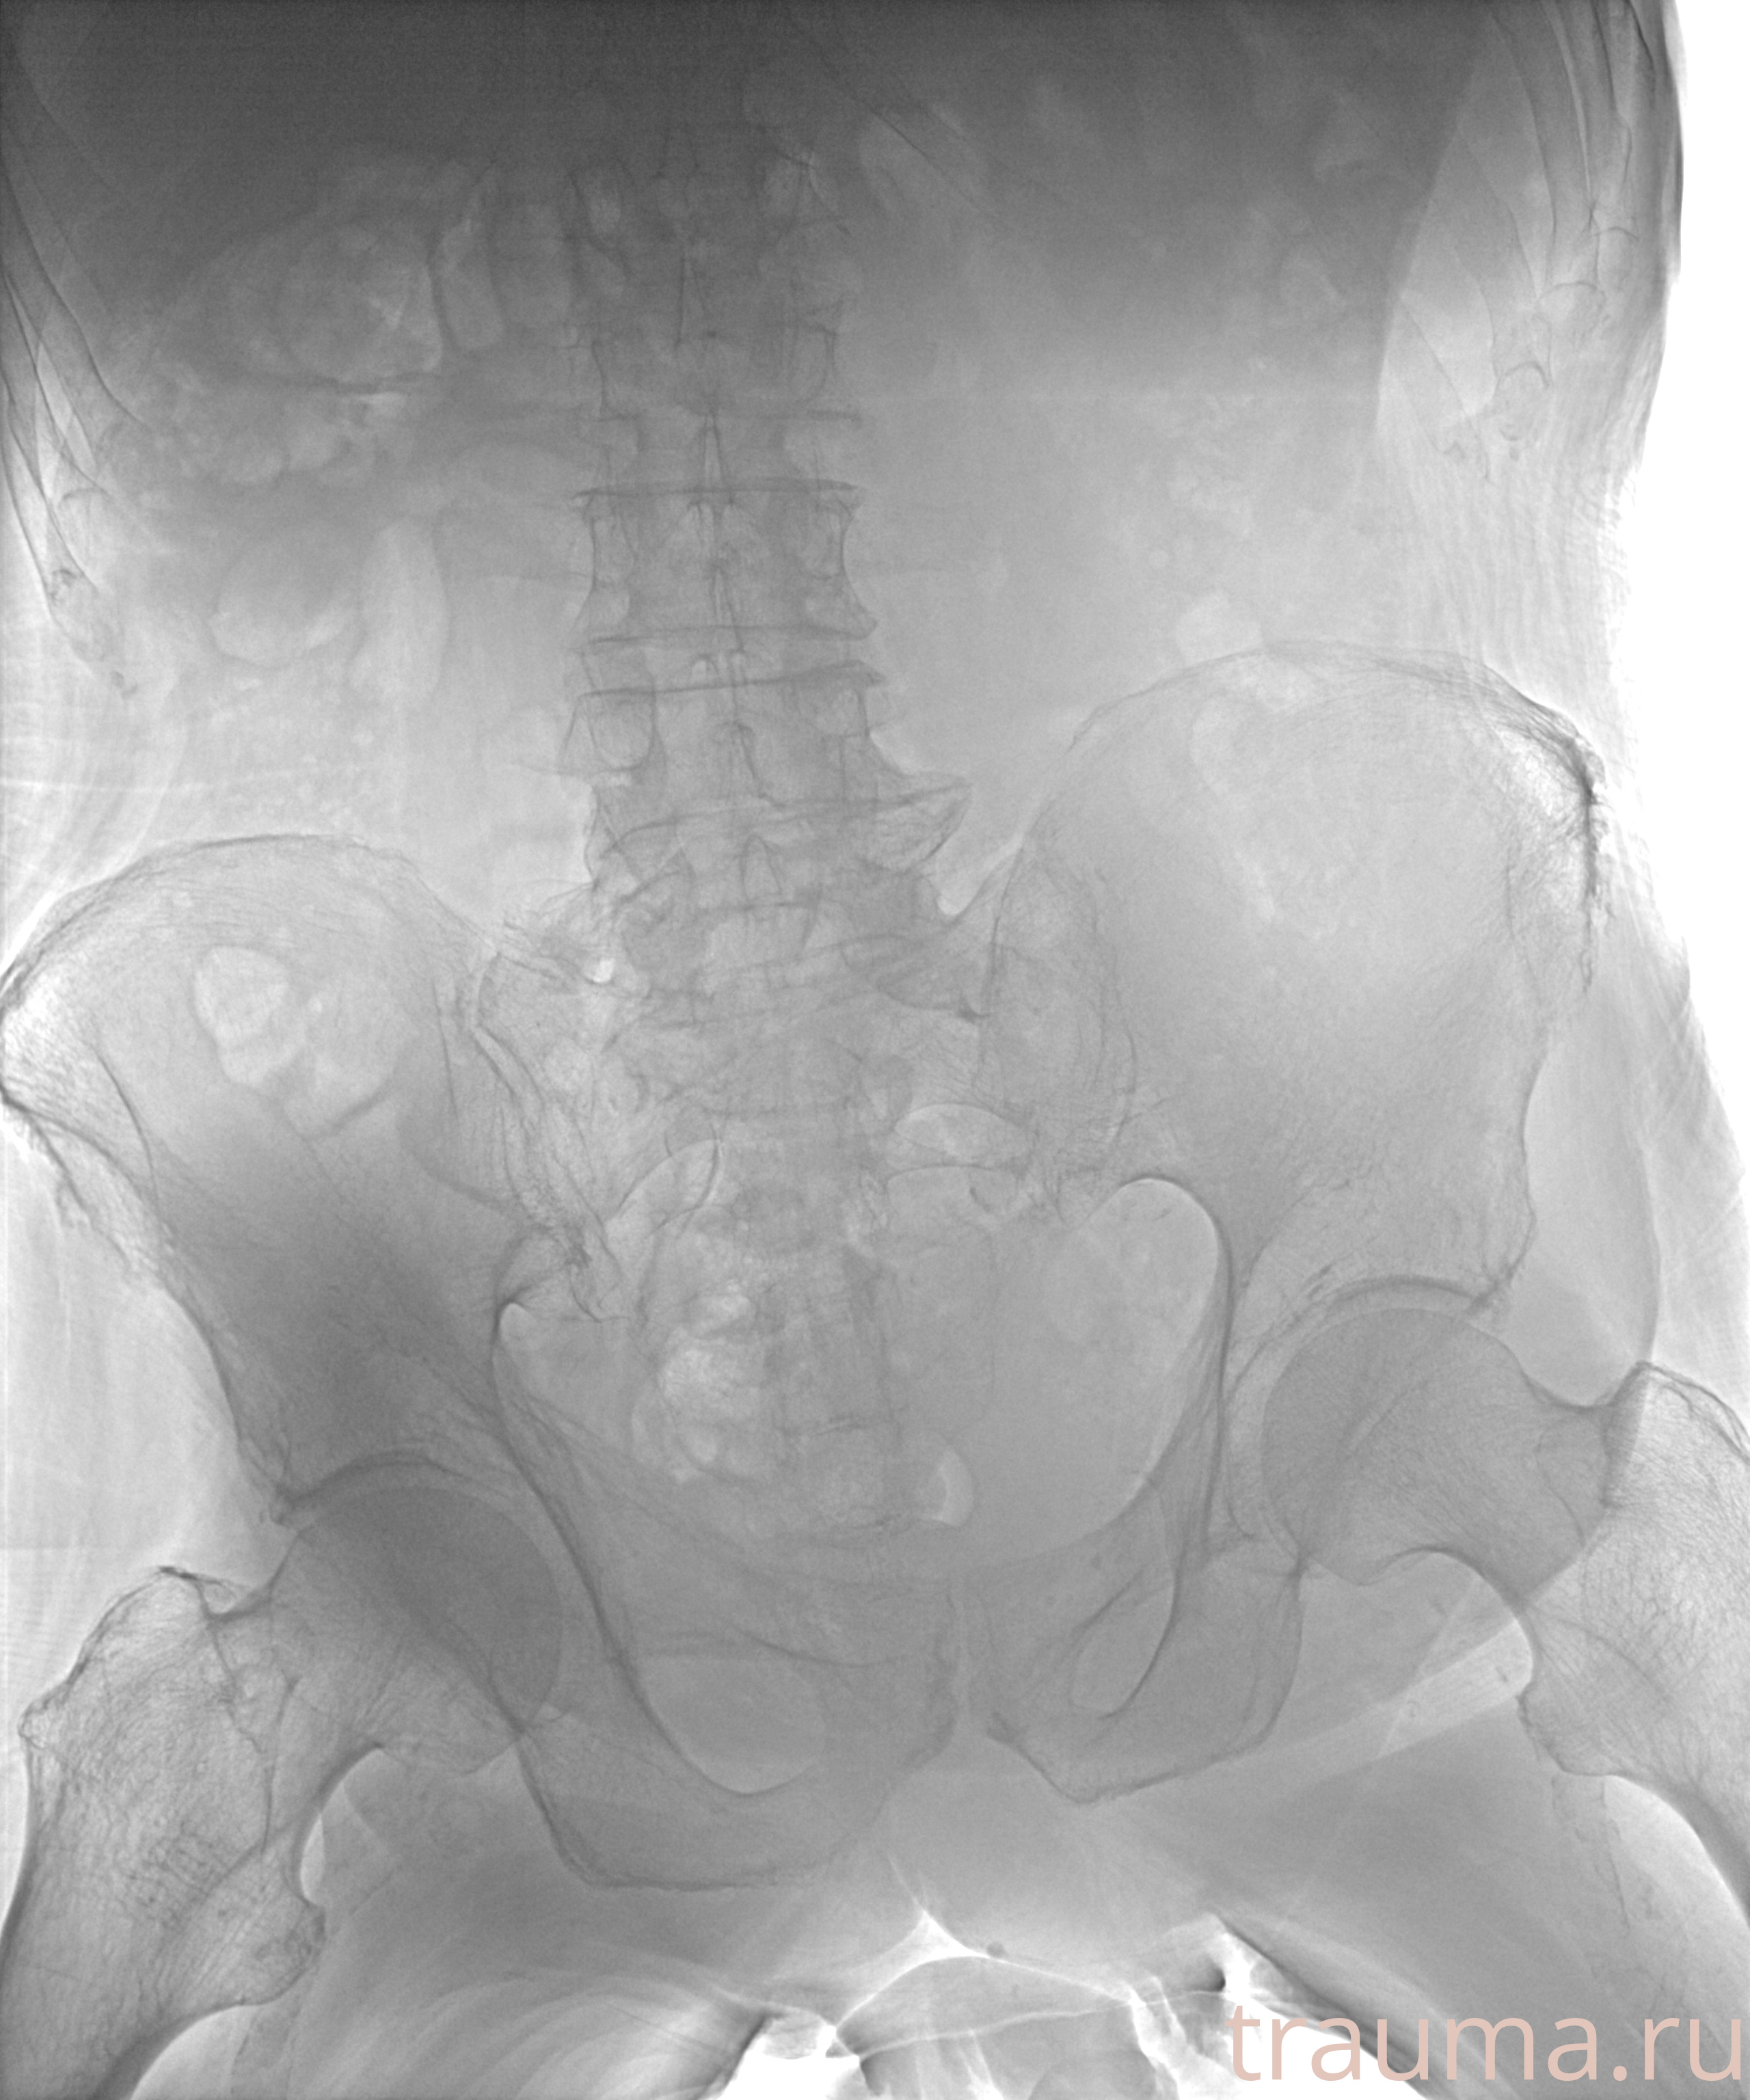

Рентгенограммы

Рентген на дому: по вашему адресу приезжает врач-рентгенолог, травматолог-ортопед с мобильным рентгеновским аппаратом, проводит диагностику травмы или заболевания, делает необходимые рентгенограммы, дает рекомендации по дальнейшему лечению. Получить качественные снимки в домашних условиях возможно благодаря уникальной методике, разработанной МосРентген Центром для института  Склифосовского